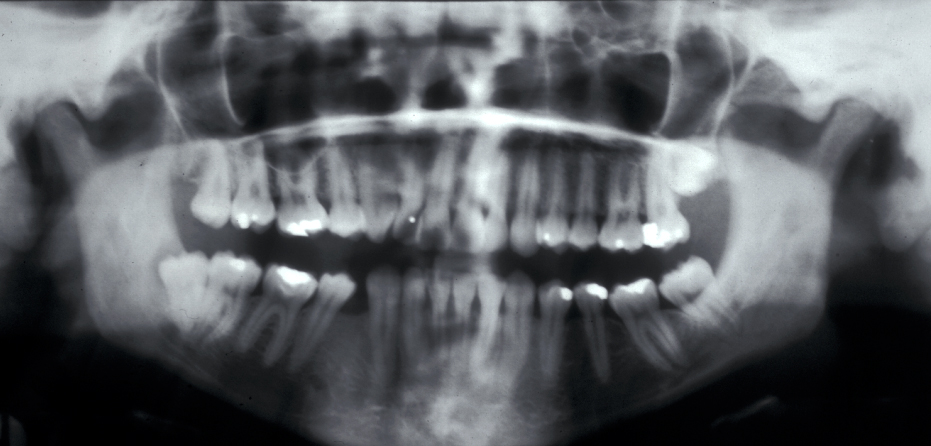

The commonest indication is recurrent pericoronitis. Pericoronitis is inflammation and infection of the mucosal flap (operculum) overlying a partially erupted tooth, usually the lower third molar (Figure 1). Pericoronitis may be acute or chronic.

Figure 2 and Figure 3 illustrate examples of indications for removal of a third molar tooth.

Assessment of the tooth is both clinical and radiographic. If somebody presents in pain, it is important to establish that this is coming from the third molar and not elsewhere. Pain is often vague, poorly localised and may be referred from another tooth, or as part of facial arthromyalgia (condition affecting the jaw joint). A dental panoramic radiograph is ideal as it helps to assess all the teeth at once. The health of the adjacent molars may influence the decision whether to remove the third molar or not. Large crowns or old restorations are all at risk of dislodgement during surgery. It is also worth considering whether alternative treatment options are available. For instance, pericoronitis due to an over-erupted upper third molar may be dealt with by extracting that tooth only, with or without operculectomy. In the presence of other teeth of poor prognosis, will it be better in the long term to save the third molar which may be used as a denture or bridge abutment in the future?

These points help to determine whether the tooth can be simply elevated or will need a surgical approach. A series of radiographs depicted in Figure 4 to Figure 8 illustrate these points further.